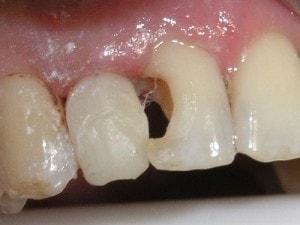

Carles removed

Enamel tapered on both preps. Enamel taper includes the entire labial of tooth #7. Many call this an apple core prep.

Apple core prep isolated with the Greater Curve Standard band

Matrix secured with Mega Bite (Discus Dental).

A portion of the matrix has been cut away intra-orally with a diamond or carbide to provide access. The distal contact opening will be established by smoothing away the matrix with a football finishing bur. -